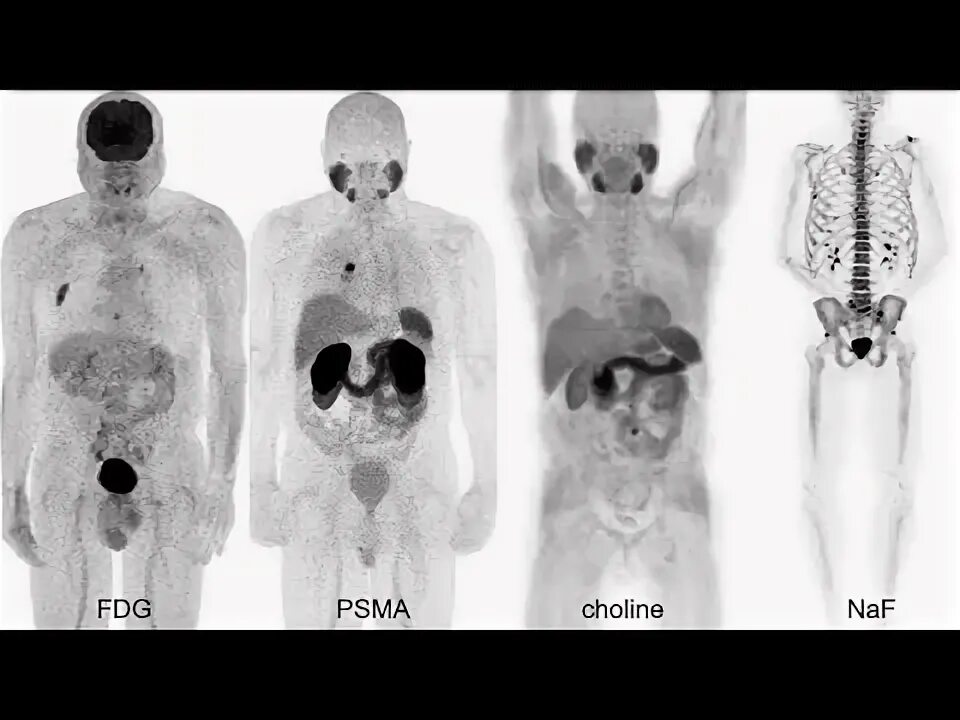

Пэт псма что это